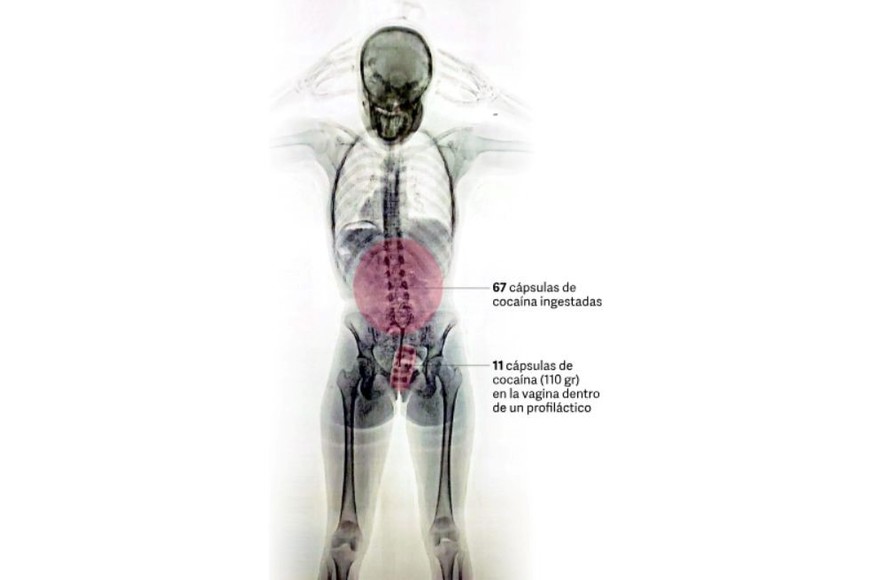

Una joven de 20 años fue detenida en los últimos días en el Aeropuerto Internacional de Ezeiza tras ser descubierta por las autoridades aeroportuarias cuando intentaba viajar a Europa con droga oculta dentro de su cuerpo. Las imágenes del escáner de rayos X revelaron la presencia de más de 700 gramos de cocaína en su vagina y su estómago.

Impresionante imagen de un escáner de rayos X: una mula tenía 78 cápsulas de cocaína en el cuerpo

La inspección dio pie a la revelación del delito: en las imágenes los efectivos observaron la posible presencia de elementos extraños en el organismo, concentrados en su zona genital.

En consecuencia, con la orden judicial en mano, la pasajera empezó a ser requisada hasta que en un momento confesó espontáneamente y manifestó que transportaba un paquete introducido vía vaginal. Concretamente, había introducido en su cuerpo un profiláctico con 11 cápsulas de cocaína, de aproximadamente 10 gramos cada una.

Como parte del procedimiento, la joven fue trasladada al Hospital de Ezeiza. Allí, bajo custodia de la PSA, estuvo incomunicada mientras evacuaba las cápsulas detectadas en las imágenes del escáner, las cuales finalmente fueron muchas más que 11: tenía otras 67 cápsulas en el sistema digestivo. En total, en su cuerpo llevaba 742 gramos de esa droga.